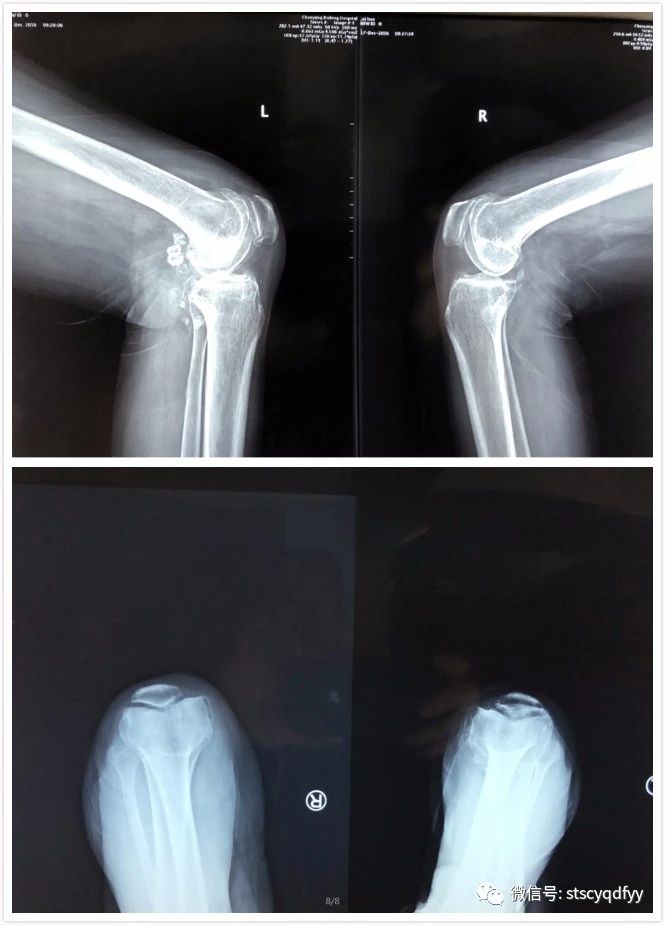

患者庄某,女性,69岁,6年来反复出现双膝关节疼痛,呈阵发性,活动后加重,休息可缓解,近2年来疼痛加剧,下蹲困难,明显影响行走,左膝尤明显,口服消炎止痛药、中药丸等不能缓解,遂到我院骨外科就诊。入院查体:左膝关节稍肿胀,左膝关节内侧间隙、髌骨周围压痛明显,关节屈伸活动度10°一100°,左膝内翻约10°;右膝关节内侧间隙压痛,关节屈伸活动度0°一110°,右膝内翻约5°。X线检查:双膝关节骨性关节炎。诊断为:“双膝关节骨性关节炎”。由我院骨外科主任林楚标收治。入院之后林主任的治疗小组拟定手术治疗方案:右膝关节单髁置换术,左膝关节单髁置换术(备左侧全膝置换术)。由于双侧同时行单髁置换技术要求较高,在我院尚属首例,为保障手术能顺利进行,达到预期治疗效果,我院请来了国内著名骨科专家──北京大学医学部临床医学骨科学博士、北京积水潭医院矫形骨科副主任医师柳剑为患者主刀。在完善各项术前准备后,于11月10日上午为患者施行手术,先行右侧单髁置换,再做左侧,术中确认左膝主要是前内侧骨性关节炎为主,最终也施行单髁置换,每侧手术时间约1小时。术后透视,双膝内翻纠正及假体位置理想,安返病房。术后第一天,拨除引流管后,患者扶助行器可以无痛行走,患者脸上满是笑容,一扫6年来痛苦的表情。家属道不完的感谢,做为医生,还有比收到这份感谢更暖心的礼物吗?